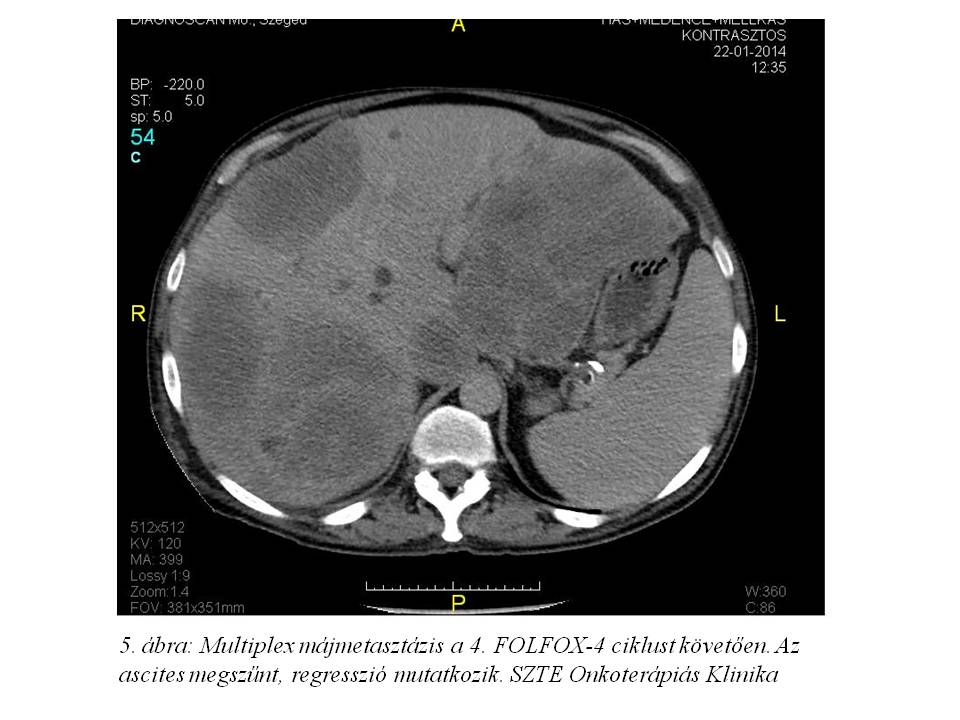

Lokális mellékhatásként postinfúziós phlebitis alakult ki, melyet szteroidos vénakenőccsel kezeltünk. Az első re-staging vizsgálatát a 4. ciklust követően végeztettük: a mellkas, has-kismedence CT vizsgálaton jó regressziót írtak le, a korábbi ascites megszűnt (2014.01.22., 5. ábra, 6. ábra), a tumormarkerek felükre, ill. tizedükre csökkentek: CA 19-9: 59.33 U/ml, CEA: 579 ng/ml. Májfunkciós értékei normalizálódtak, az ALP 1158 U/l-re csökkent.